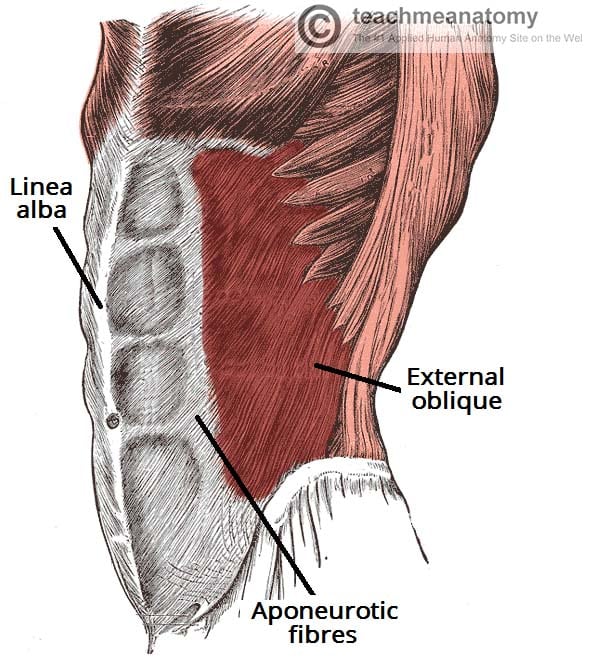

Muscles of the Anterolateral Abdominal Wall

- Layers and Functions:

- External oblique muscle

- Supports and compresses abdominal viscera

- Flexes and rotates the trunk

- Internal oblique muscle

- Transversus abdominis muscle

- External oblique muscle

Rectus Sheath

- Components:

- Rectus abdominis with tendinous intersections

- Linea alba (interlacing fibers forming the rectus sheath)

- Semilunar line

- Arcuate line (notable absence of transversus abdominis aponeurosis inferiorly)

*Note from an M2: You will be tested on these lines. Know which differences occur below and above these lines.